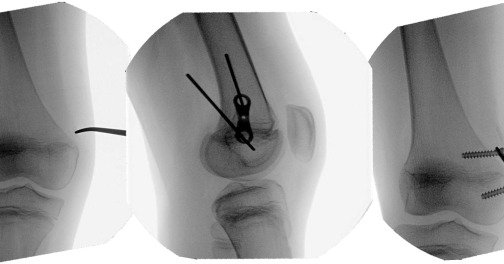

πŸ§’This systematic review identifies and examines current applications, techniques, and outcomes of guided growth for paediatric knee pathology, giving a comprehensive approach to these procedures. πŸ–ŠοΈ Read more πŸ‘‰

Guided growth has fundamentally transformed paediatric knee surgery, offering a less invasive alternative to manage paediatric knee pathology and lower limb angular deformities.A better understanding...